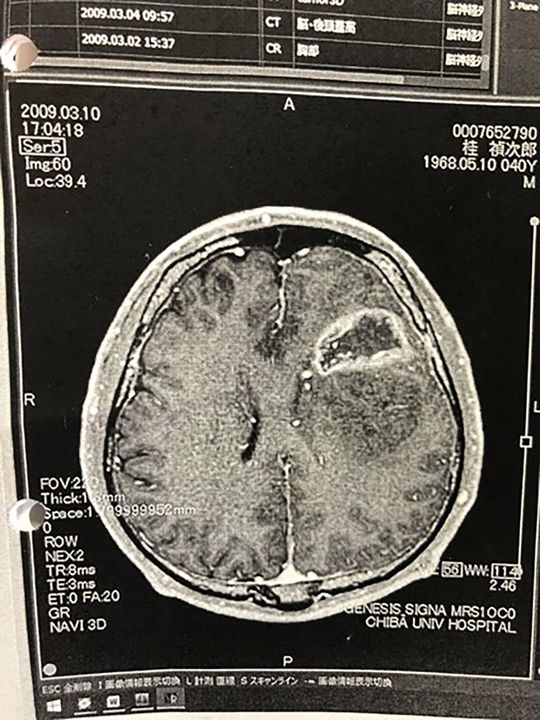

脳の画像は下からとるので左右が逆になる。桂禎次郎の2009年3月10日のMRI画像。左脳にある白い環は「リングエンハンス」といい、膠芽腫の典型的な画像。(写真=『がん征服』より)